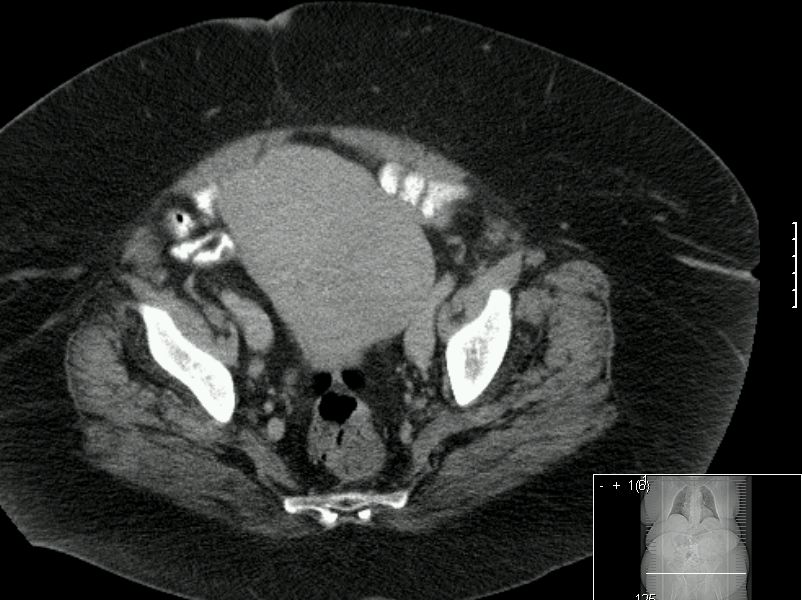

64-jährige adipöse Frau (BMI 57) mit stark vergrößerter Gebärmutter.